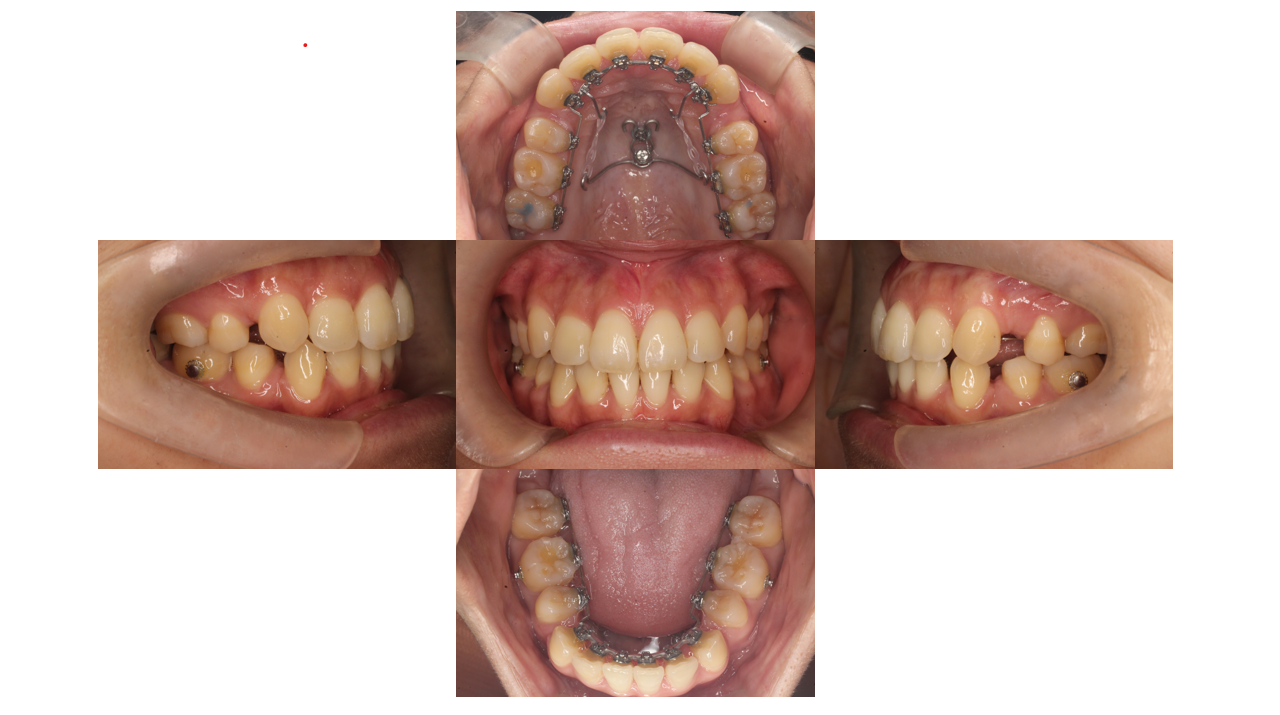

6か月経過

叢生、出っ歯

半年が経過すると初診時気になっていた前歯の凸凹はもう残っていません。

角度のついていた前歯も真っ直ぐになってきています。